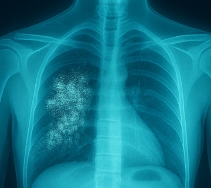

폐결핵 증상 vs 기타 결핵 유형

구분 폐결핵 증상 기타 결핵 유형 전염성 매우 높음 낮음 (비전염성) 대표 증상 기침, 가래, 발열, 체중 감소 장 결핵(복통), 척추 결핵(요통), 뇌수막 결핵(두통) 진단 흉부 X-ray, 객담 검사 CT, 조직검사 등 복합 검사 결핵 증상은 폐에 국한되지 않기 때문에 다른 장기에서 발생한 비정형 결핵 증상도 주의 깊게 살펴야 합니다.

결핵 증상이 의심된다면 보건소나 병원을 통해 객담 검사, X-ray 등 정밀 진단을 받는 것이 필수입니다.